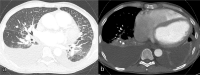

A wide spectrum of conditions, from life-threatening to non-urgent, can manifest with acute dyspnea, thus presenting major challenges for the treating physician when establishing the diagnosis and severity of the underlying disease. Imaging plays a decisive role in the assessment of acute dyspnea of cardiac and/or pulmonary origin. This article presents an overview of the current imaging modalities used to narrow the differential diagnosis in the assessment of acute dyspnea of cardiac or pulmonary origin. The current indications, findings, accuracy, and limits of each imaging modality are reported. Chest radiography is usually the primary imaging modality applied. There is a low radiation dose associated with this method, and it can assess the presence of fluid in the lung or pleura, consolidations, hyperinflation, pneumothorax, as well as heart enlargement. However, its low sensitivity limits the ability of the chest radiograph to accurately identify the causes of acute dyspnea. CT provides more detailed imaging of the cardiorespiratory system, and therefore, better sensitivity and specificity results, but it is accompanied by higher radiation exposure. Ultrasonography has the advantage of using no radiation, and is fast and feasible as a bedside test and appropriate for the assessment of unstable patients. However, patient-specific factors, such as body habitus, may limit its image quality and interpretability. Advances in knowledge This review provides guidance to the appropriate choice of imaging modalities in the diagnosis of patients with dyspnea of cardiac or pulmonary origin.